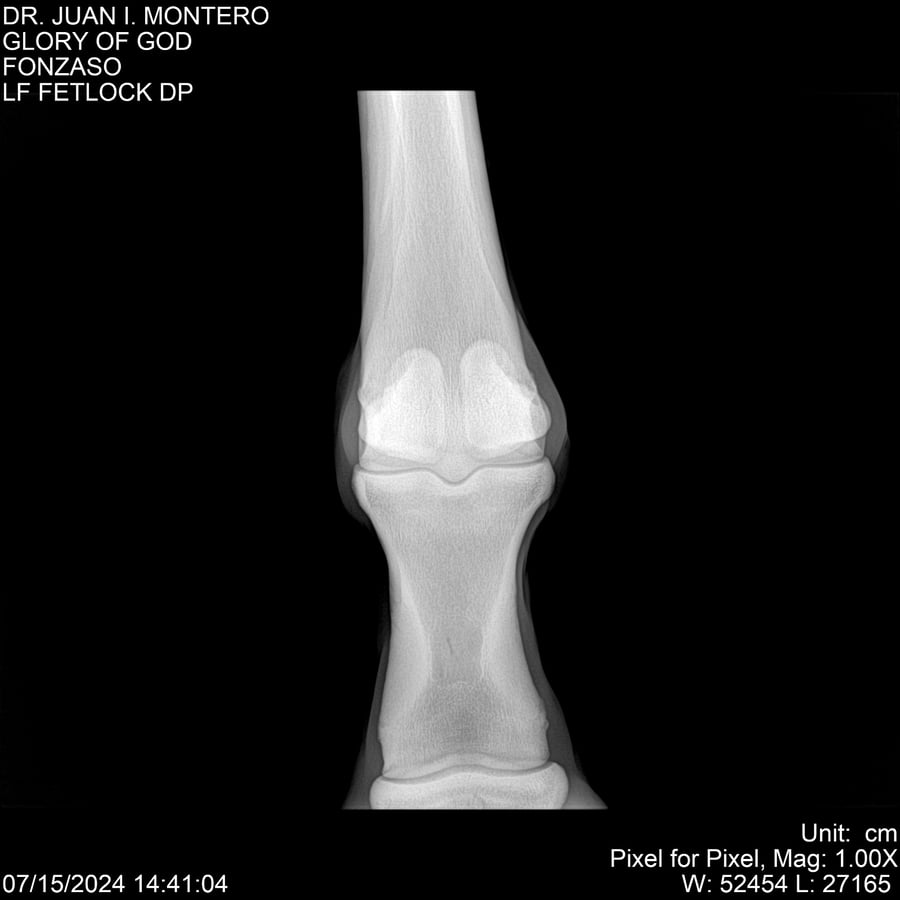

LOTE 10, GLORY OF GOD 🔥 🔥 🔥 Lote Anterior Volver al remate Lote Siguiente Ficha Contacto Montevideo - Ficha del Lote Identificador: #281389 Categoría: Yeguarizos Montevideo - 115 Visualizaciones ClicData Contacto Empresa: Abelenda N. R., Walter Hugo Nombre*: Teléfono* : E-mail* : Mensaje Enviar Registrese gratis Este contenido Exclusivo está disponible sólo para usuarios registrados Ingresar